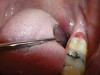

The angled handpiece of the CO2 laser was held perpendicular to the target lesion (Figure 4) and the ablation of the inflamed tissue began (Figure 5). The dental surgeon was careful to avoid contact between the laser beam and the tooth enamel. (Note: In this case, the inflamed tissue was located distally from the involved molar. There was no direct contact of the beam with the tooth, as the surgeon was careful not to hit the enamel. However, if an operculum covers part of the tooth, an adaptive tool (for example, a wax spatula) needs to be inserted between the tissue and the tooth to prevent possible damage. For an inexperienced CO2 laser surgeon, it is important and highly recommended to always shield the tooth during the procedure.6)

Fig 4. The angled handpiece of the CO2 laser was held perpendicular to the target lesion.

Figure 4